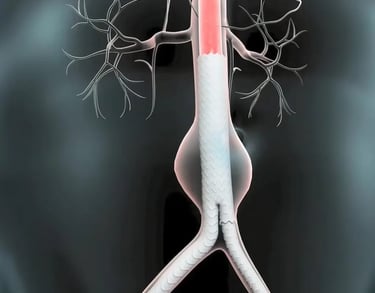

Aortic & Structural Heart Diseases

From aortic aneurysm evaluation to structural heart interventions, Dr. Anil’s expertise ensures early detection and minimally invasive treatment using the latest imaging and device technologies.